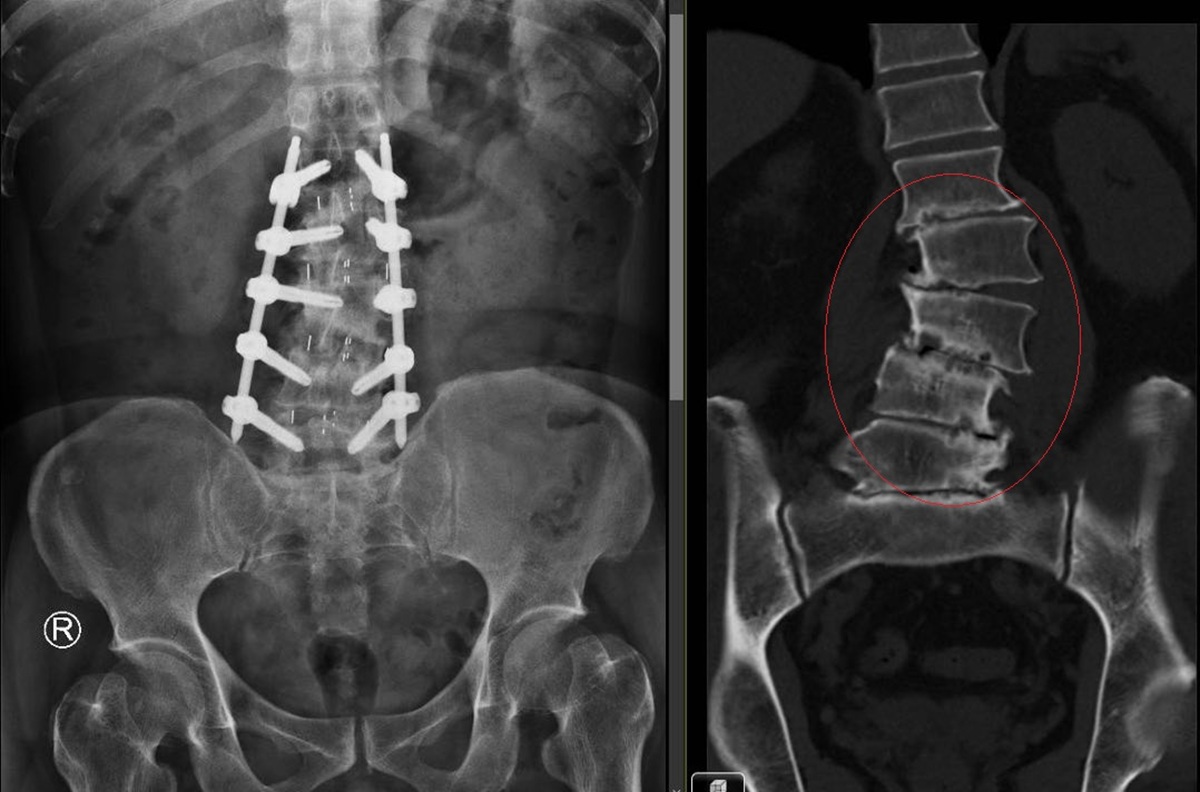

▲陳柏辰表示,經影像檢查發現,胡先生第1至第5節腰椎的椎間盤已嚴重磨損退化,磨到扁平,導致脊椎側彎與滑脫。(圖/彰化醫院提供)

陳柏辰表示,經影像檢查發現,胡先生第1至第5節腰椎的椎間盤已嚴重磨損退化,磨到扁平,導致脊椎側彎與滑脫,這正是長年背痛、無法多走路的病灶根源。

陳醫師表示,他為胡先生進行新式脊椎微創手術(OLIF),除了清除受損的椎間盤,並植入高分子聚合物的「斜位融合支架」,支撐力是傳統支架的3至5倍,穩固地將萎縮的椎間盤空間撐開,再配合骨釘植入,成功矯治了胡先生的脊椎側彎。